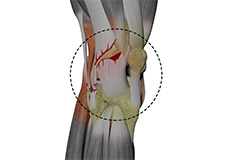

Articular Cartilage Injury

Articular or hyaline cartilage is the tissue lining the surface of the two bones in the knee joint. Cartilage helps the bones move smoothly against each other and can withstand the weight of the body during activities such as running and jumping.

Chondral or Articular Cartilage Defects

The articular or hyaline cartilage is the tissue lining the surface of the two bones in the knee joint. Cartilage helps the bones move smoothly against each other and can withstand the weight of your body during activities such as running and jumping.